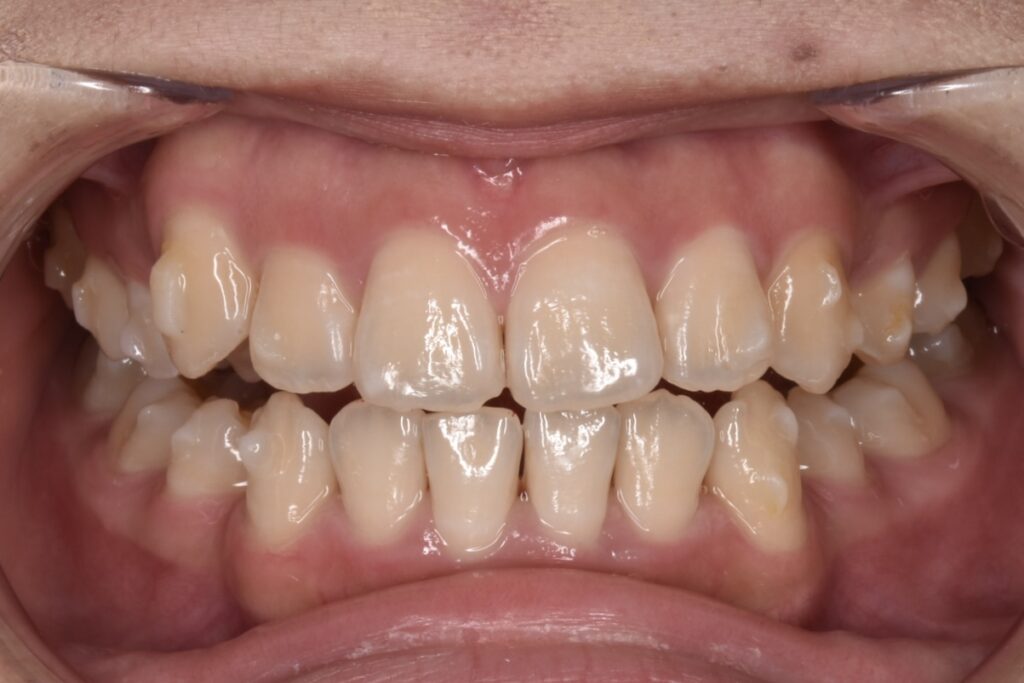

現状38枚目(矯正開始後10ヶ月)

現在矯正開始から38週経過し38枚目になっています。追加アライナーなし、順調に経過しています。八重歯感もだいぶ改善してきましたね。噛み合わせは本人様は全然気にならない様ですが最後に調整していきます。追加アライナーとゴムかけなどです。